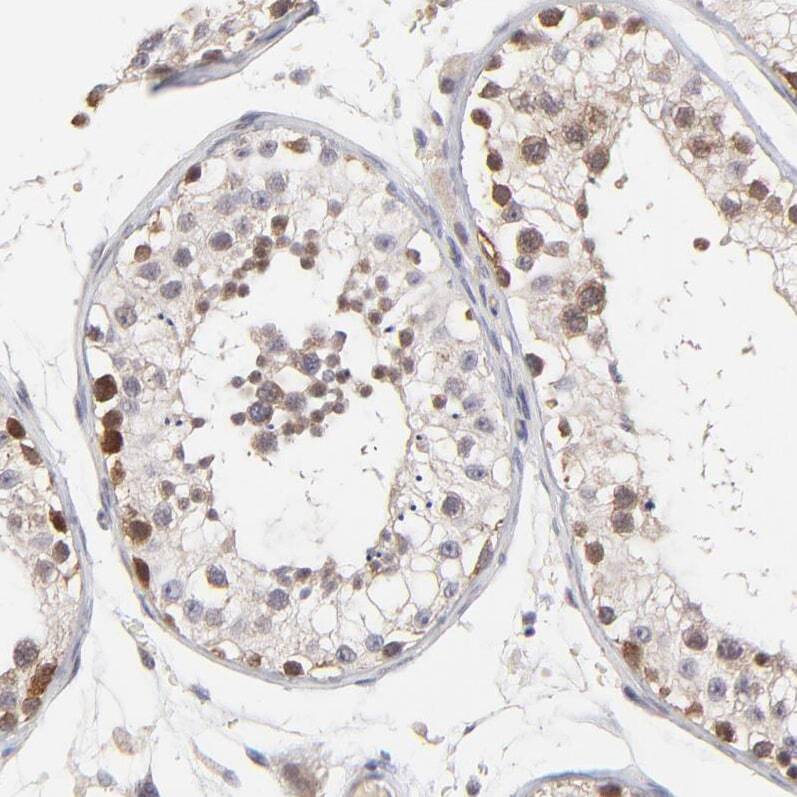

- Immunohistochemical staining of ZNF177 in human testis using ZNF177 Polyclonal Antibody (Product # PA5-51835) shows weak to moderate nuclear and cytoplasmic positivity in a subset of cells in seminiferous ducts.